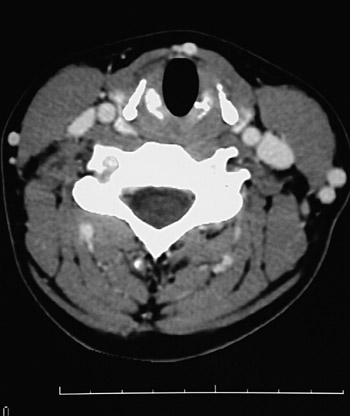

This is a normal axial head and neck CT scan demonstrating the thyroid cartilage and cricoid cartilage and sternocleidomastoid muscle and external jugular vein and levator scapulae muscle and semispinalis muscle and splenius capitis muscle and trapezius muscle and internal jugular vein and common carotid artery.